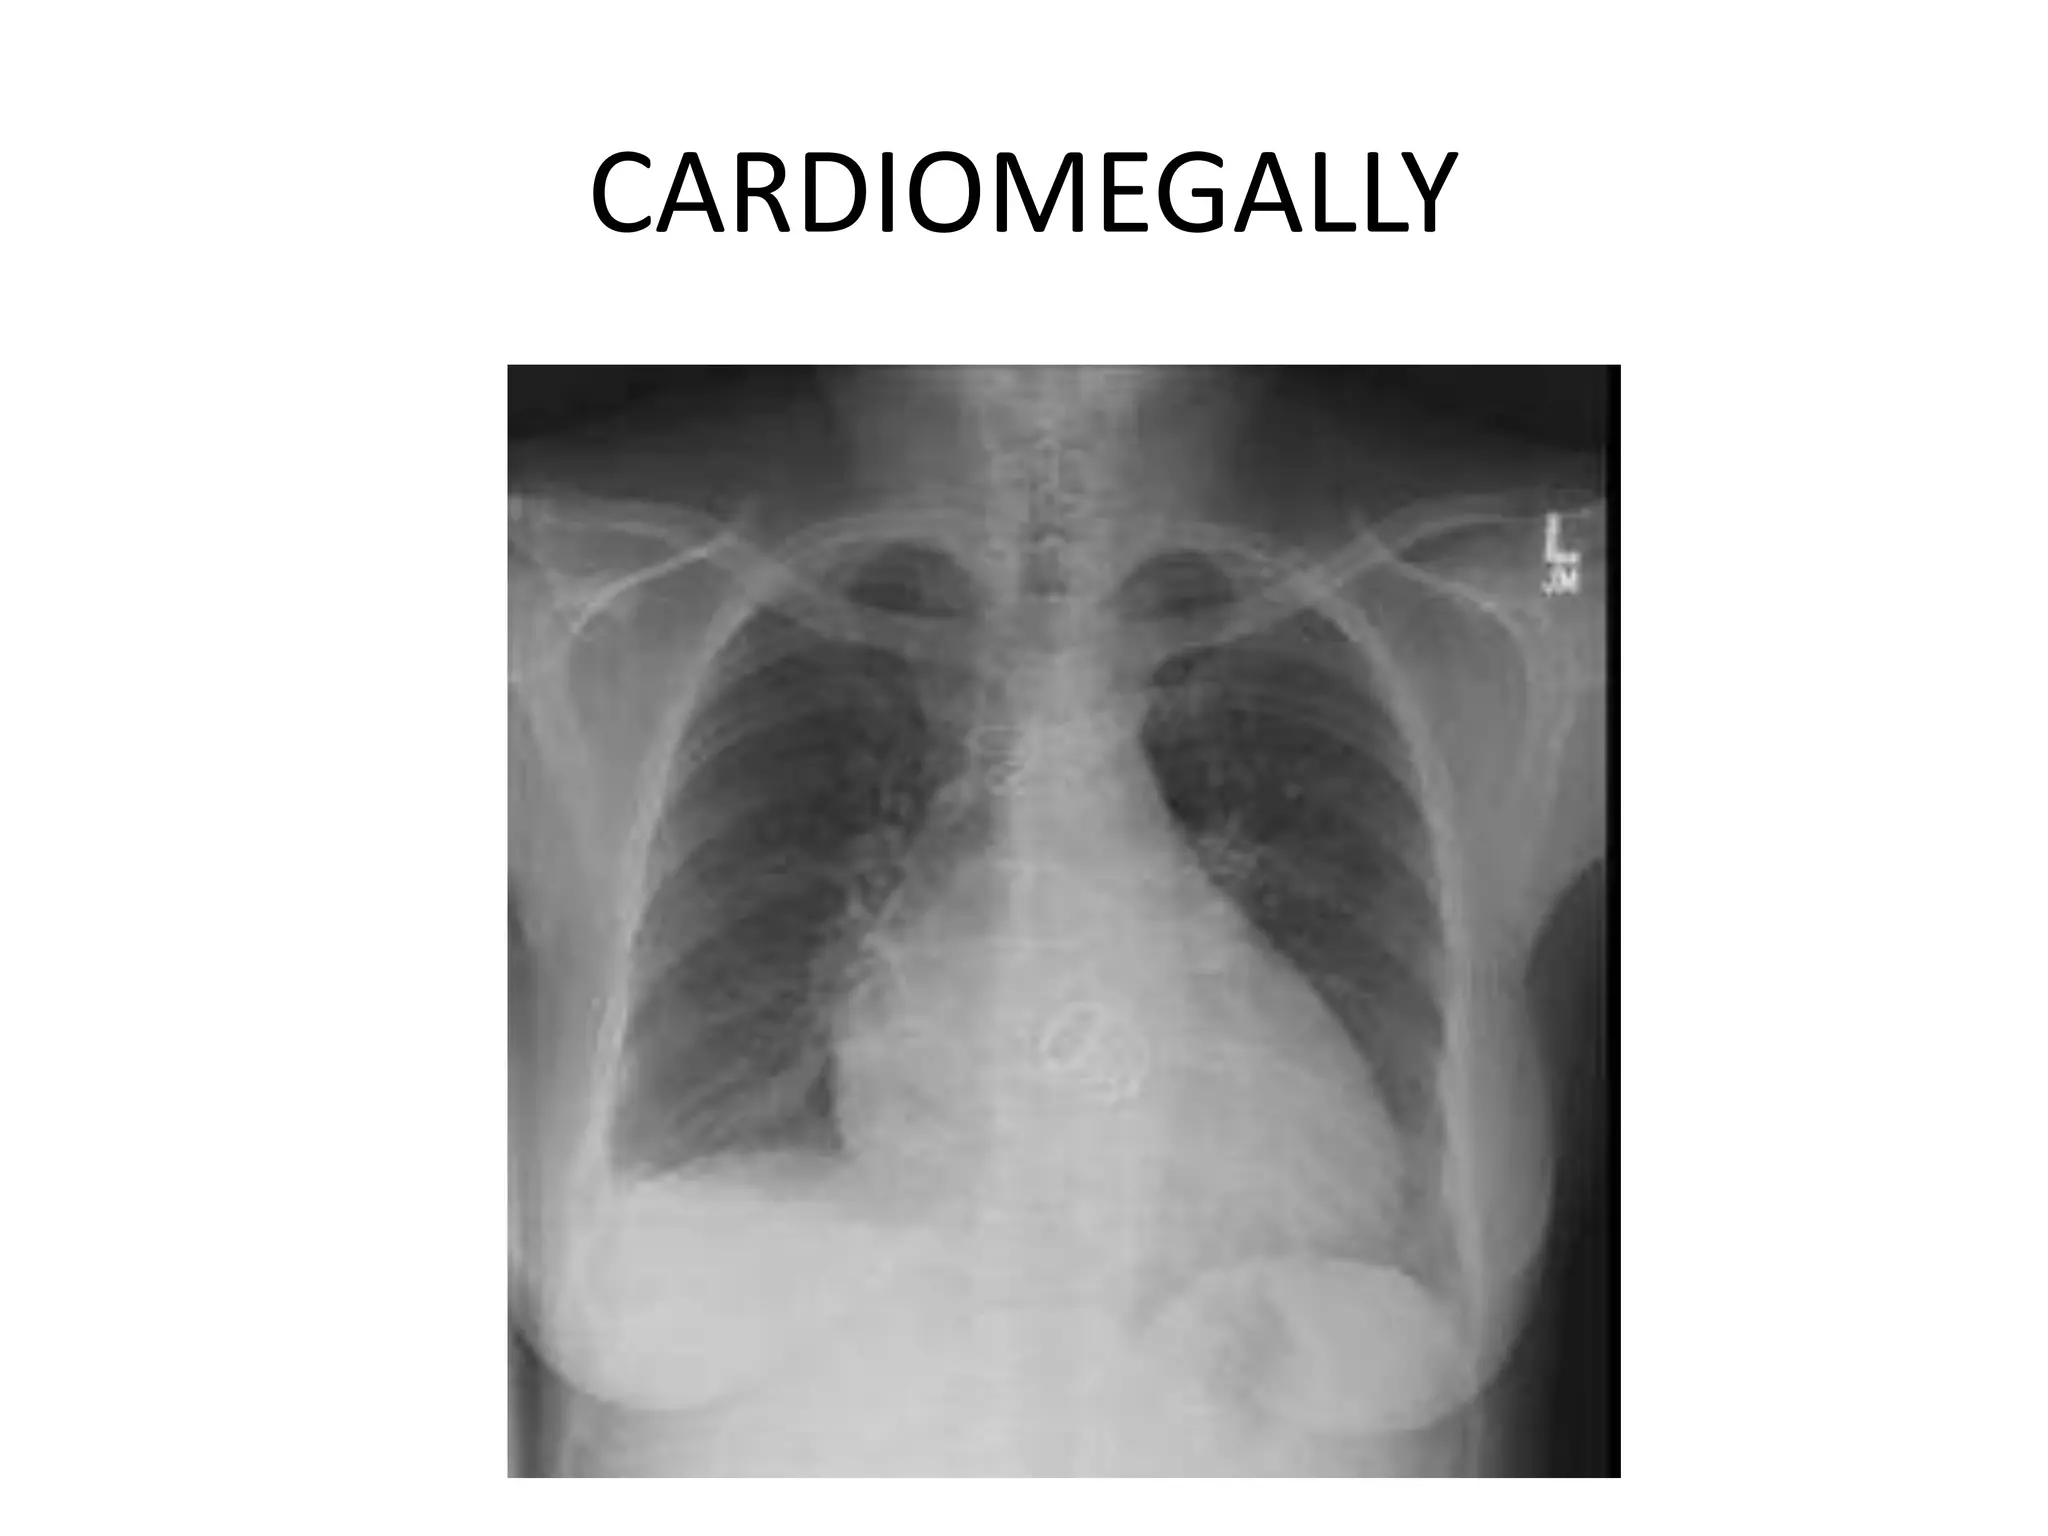

This document provides an overview of key topics in chest x-rays, ECG readings, medical instruments, drugs, and clinical pictures commonly seen in medical orientation classes. It lists various chest x-ray findings like pleural effusion, pneumonia, and pulmonary edema. It also outlines different ECG waves and conditions such as atrial fibrillation, heart blocks, and left ventricular hypertrophy. Common medical instruments like oropharyngeal airways, IV cannulas, and Foley catheters are identified. Examples of anti-tuberculosis therapy, steroids, and clinical pictures including butterfly rash and Cushing's face are briefly covered.